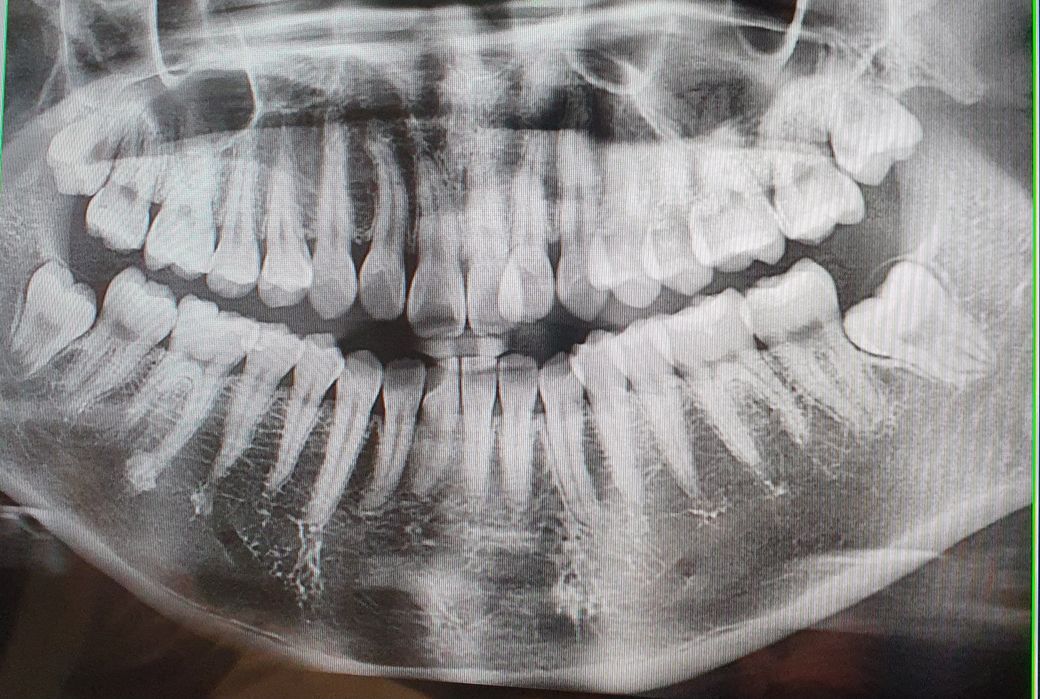

사랑니 발치.. 필요할까요? 궁금해요

사랑니 발치가 필요한지 궁금합니다.

치과 의사쌤 두 분은 똑바로 잘 자라고 있다면서 뽑을 필요 없다고 하셨는데요.

제가 보기엔 옆 이빨을 치면서 나오는 거 같은데 똑바른건지 궁금합니다.

요즘 사랑니 나는 쪽 맨 뒤 잇몸이 붓는 것 같아서 신경쓰여요.

사진에 보이는 사랑니의 경우에는 앞에 있는 치아에 영향을 미칠 가능성이 낮아 보입니다.

게다가 아래 사랑니는 잇몸안에 있기 때문에 충치나 치주질환의 가능성도 낮아 보이기 때문에 좀더 기다려 보시는것이 좋습니다.

사랑니 4개가 다 잘 나오고 있습니다.

왼쪽 아래 사랑니의 경우, 앞의 치아에 가깝게 나오고 있는것처럼 보이지만, 사진상으로 저렇게 보이는것일 뿐, 실제로는 앞의 치아를 건들지 않고있을 가능성도 있습니다

조금더 기다리면서, 어떻게 올라오는지 봐야, 앞의 치아를 건드리는지에 대해 더 잘 알 수 있습니다.

위의 사랑니의 경우, 조금더 올라올때까지 기다리면서, 통증이 심하고 관리가 안된다면 발치할 수 있겠습니다.

사진이 입체가 아닌 평면이기때문에 정확한건아니지만

사진을 봐서는 똑바로 나오고 있는것 같습니다.